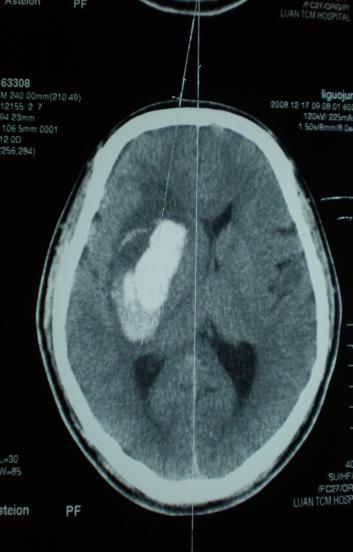

脑出血3种微创手术(穿刺、显微、内镜)简介

六安市中医院神经外二科经过20多年的临床实践,结合国内外脑出血研究的最新进展,对有手术指证的脑出血患者实施微创手术:创伤小、恢复快、效果好;有3种微创手术方式:穿刺置管引流、显微(锁孔)手术、内镜锁孔手术;并为患者提供个性化选择。现简介如下:

一、 穿刺置管引流

方法:局麻、锥颅、置管、引流

优点:简单、有效